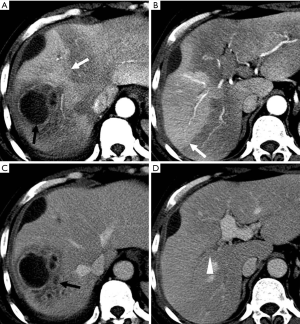

HAPS secondary to HCC may occur through the following routes: (I) transvasal: early invasion and tumor thrombi formation in the branches of the portal vein is frequent in HCC. Since the hypervascular tumor thrombi are supplied by the vasa vasorum of the portal vein wall (21), hepatic arterial flow may drain into the lumen of the portal vein from tumor thrombi (11). These usually manifest as a central and severe HAPS (Figure 5). (II) Transplexal: HCC may sometimes be associated with compromised portal vein flow, and a subsequent HAPS via the transplexal route may be involved (2,16). Arterial blood shunts to the portal venous and hepatic sinusoids via the peribiliary plexus in these cases and usually presents with moderate HAPS (Figure 6). (III) Transsinusoidal: less frequently, retrograde arterial blood shunts into branches of the portal vein via the hepatic sinusoids because of the compromised hepatic venous flow in HCC, which generally constitutes a mild and peripheral HAPS. (IV) Transtumoral: the arterial blood supply to the HCC can be shunted through the tumor venous into peripheral portal veins (10).

Evaluation of HCC with HAPS

HAP results in the heterogeneous enhancement of the hepatic parenchyma. The enhancement of HCC will be significantly reduced in the situation of serious HAPS due to a large amount of contrast medium flowing into the portal vein through the shunt. On the equilibrium phase, the characteristic washout and extension of the tumor can nonetheless be identified accurately. The equilibrium phase is most useful for diagnosis and delineation of HCC as an area of heterogeneous low density (intensity) (Figures 7,8). The presence of HAPS is not necessarily a contraindication to resection, ablative therapies or other liver-directed therapies, and the degree of resection or other therapy can best be determined in the equilibrium phase (22).